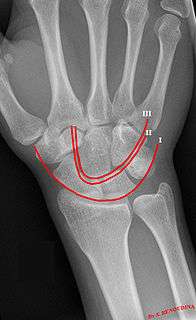

Gilula carpal arcs.

Gilula's lines are three arcs drawn on an AP radiograph of the wrist used to assess the alignment of the carpus.

There should be no step-off in the contour of the lines when drawn on a normal wrist.

| First arc | running along the proximal convexity of the scaphoid, lunate and triquetrum |

| Second arc | running along the distal concavities of the scaphoid, lunate and triquetrum |

| Third arc | running along the proximal curvatures of the capitate and hamate |